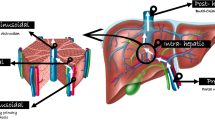

Surgical non-selective portosystemic shunts (such as mesocaval and portocaval shunts) help to reduce portal hypertension but are associated with higher rates of clinical complications such as hepatopulmonary syndrome, encephalopathy or hyperammonemia, which are undesirable in children [17]. Otherwise, the most common selective shunt is the distal splenorenal Warren shunt. The distal splenorenal shunt allows decompression of gastroesophageal varices in both short gastric veins and splenic veins and preserves antegrade perfusion to the liver with less likelihood of clinical consequences [18]. Currently, meso-Rex bypass is the gold standard treatment for pre-hepatic portal vein thrombosis in children with preserved anatomy [21]. Meso-Rex bypass is a venous conduit, usually an autologous graft from the internal jugular vein, connecting the infra-pancreatic superior mesenteric vein to the intrahepatic left portal vein at the Rex recess, the remnant of embryonic umbilical vein. This bypass restores physiological hepatopetal portal flow, avoiding dangerous complications of portosystemic shunting [17, 20, 21].

Preoperative imaging is pivotal in the setting of surgical planning. While CT and magnetic resonance (MR) angiography are essential to confirm the pre-hepatic portal vein thrombosis diagnosis and evaluate both the extension of portal cavernoma and size of the extra- and intrahepatic portal system, particularly of the superior mesenteric vein, wedged hepatic venous portography is the mainstay imaging examination for assessing the surgical feasibility of the meso-Rex bypass [17, 20]. Wedged hepatic venous portography consists of retrograde (indirect) phlebography of the intrahepatic portal venous system performed through wedged catheterization of the suprahepatic veins via the right internal jugular vein under general anesthesia. The goal of the procedure is to evaluate the patency of both the Rex recess and left portal vein and to assess the reciprocal communication between right and left intrahepatic portal veins (Fig. 2).

Specifically, Bertocchini et al. [22] categorized the radiologic findings of wedged hepatic venous portography into five specific imaging patterns (A to E), proposing meso-Rex bypass surgery only for children with patent Rex recess (subtypes A to C) and opting for conservative follow-up for clinically stable children or portosystemic shunt creation in cases of complicated portal hypertension. Therefore, this preoperative examination allows the identification of children who are eligible for meso-Rex bypass and thus avoids unnecessary surgical exploration for those with thrombosed Rex recess [22]. Moreover, the hepatic venous pressure gradient can be measured simultaneously to provide important supportive diagnostic information, for instance during the transjugular liver biopsy procedure. Although available data on hepatic venous pressure gradient measurement in the pediatric population are very limited, pressure threshold ≥10 mmHg is predictive of the formation of varices and ≥12 mmHg is associated with decompensation with ascites or variceal bleeding, similar to findings in adults [17, 23, 24]. Although technically feasible, direct portography through transhepatic percutaneous access to the left portal venous system is not recommended because of the risk of vascular complications at the surgical anastomosis site [17].

Meso-Rex bypass is the recommended option for children with pre-hepatic portal vein thrombosis but requires normal liver architecture to ensure long-term patency [24]. Moreover, interventional radiology is usually the first treatment choice in cases of stenosis or occlusion of the shunt through angioplasty, stenting or thrombectomy [17, 21] (Fig. 3). Some authors have also described recanalization of the portal system using different techniques [25,26,27].